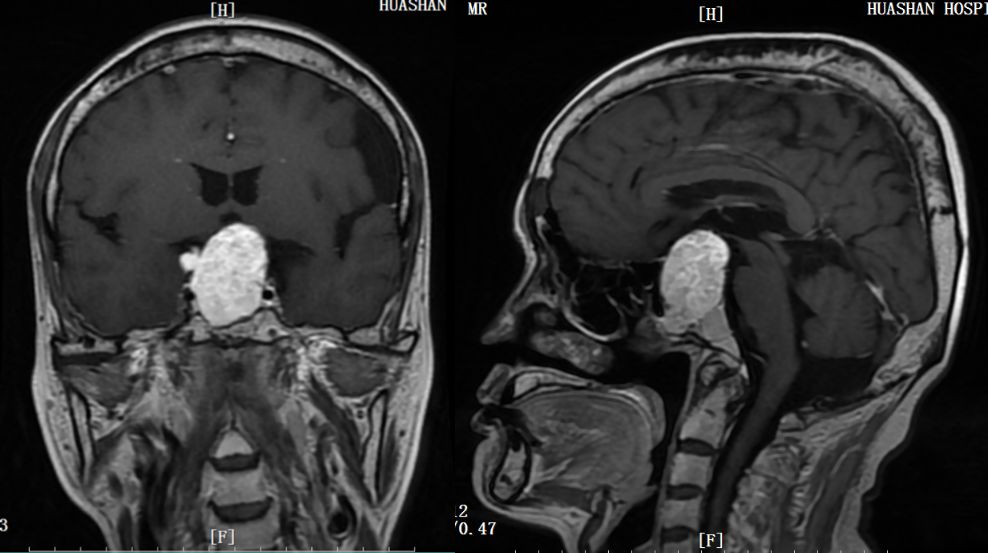

患者老王今年50岁,来自河南。2013年起老王出现消瘦,并有心慌、怕热、手抖,然而这没有引起他的重视。随着症状加重,三年之后。老王在当地医院查出有心房颤动,是一种心律失常,可是治疗后心脏不适没有明显改善。直到2019年5月,老王不幸遇到车祸,到医院做头颅CT和磁共振,居然发现有个巨大的垂体瘤,并且是一种罕见的分泌促甲状腺激素的腺瘤,正是因为这个肿瘤导致老王出现了心脏疾病。由于垂体促甲状腺激素腺瘤在临床上极少见,常引起误诊、漏诊,延误了治疗时机。

老王随后慕名求诊于华山医院神经外科王镛斐教授。考虑到患者病情较重、病程漫长,需进行充分的术前评估与准备,王教授立即联系了华山垂体融合病房的内分泌科,内分泌通过功能性垂体瘤诊疗绿色通道迅速安排患者入院评估。老王于2019年6月收入内分泌科,经一系列详细检查,明确是垂体促甲状腺激素腺瘤。由于肿瘤巨大,已明显压迫视神经,导致视力下降和视野缺损,应尽快接受手术治疗。内分泌科张朝云教授与王镛斐教授进行了第一次病例讨论,考虑到患者甲亢没有得到控制,甲状腺激素水平很高,此时手术风险大,很容易导致甲状腺危象的发生,而甲状腺危象的死亡率高达20%以上。内外科讨论后决定了治疗方案:先由内分泌科尽快控制甲亢,然后予以手术切除肿瘤。